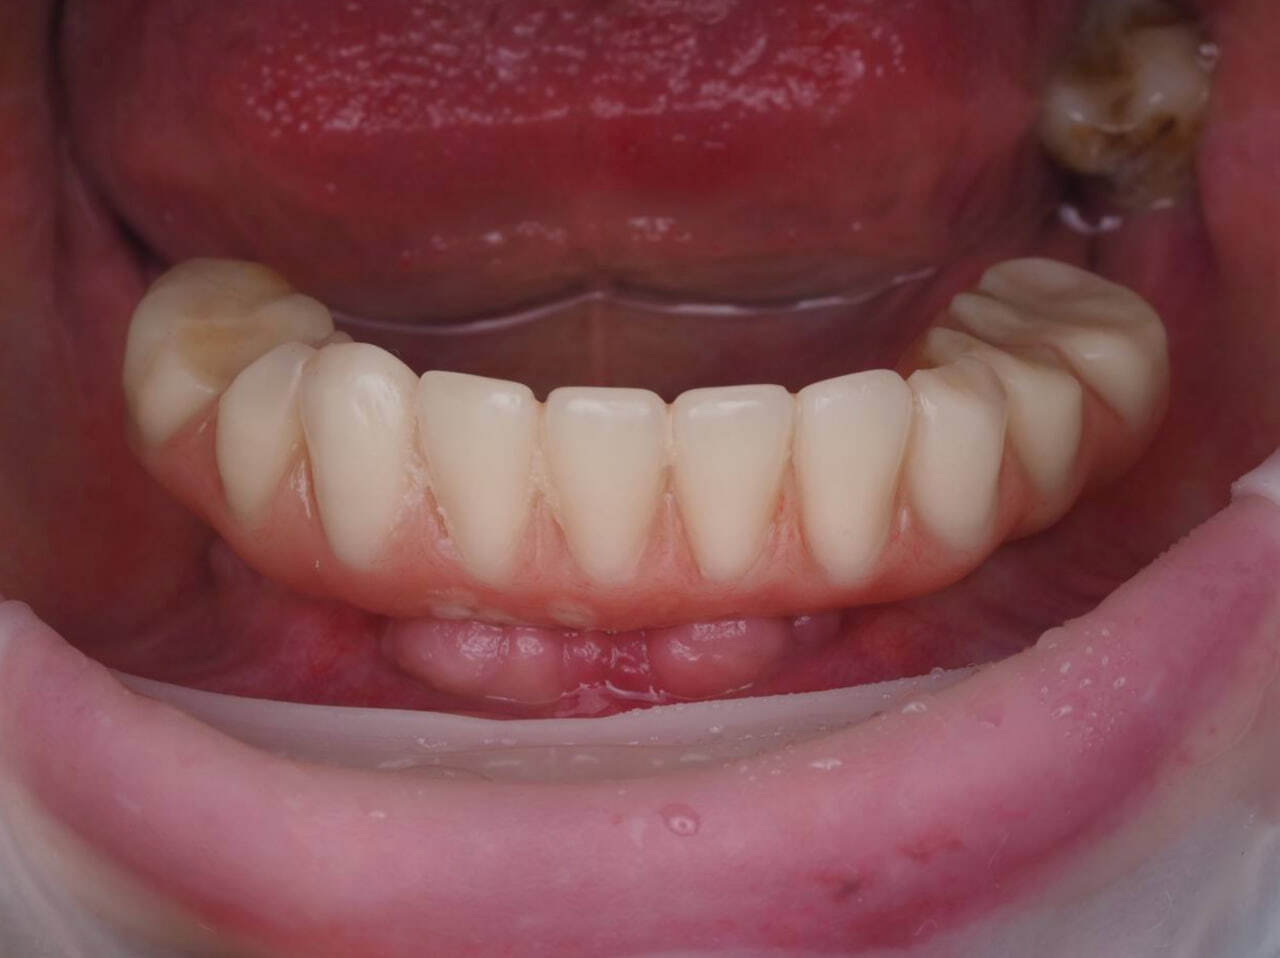

После снятия адаптационного временного протеза прекрасное состояние мягких тканей.